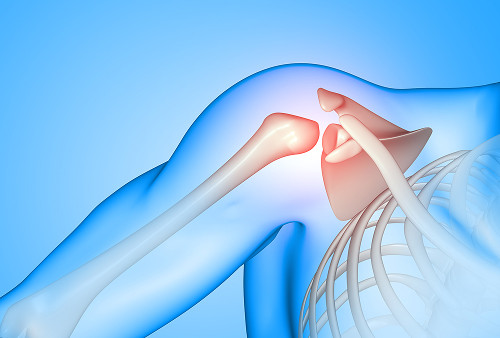

Проксимальные переломы

Проксимальные – возникают в верхней части плечевой кости – в области головки, анатомической и хирургической шейки. Чаще всего страдает пожилой человек при падении на вытянутую руку. При таких травмах часто наблюдается смещение отломков, требующее точной фиксации. В ряде случаев врач применяет гипс при переломе плечевой кости, однако при выраженном смещении выполняется хирургический остеосинтез с использованием пластины или винтов.

Повреждение головки плеча опасно тем, что может затрагивать плечевой сустав, вызывая последующее ограничение движений, боль и деформацию.